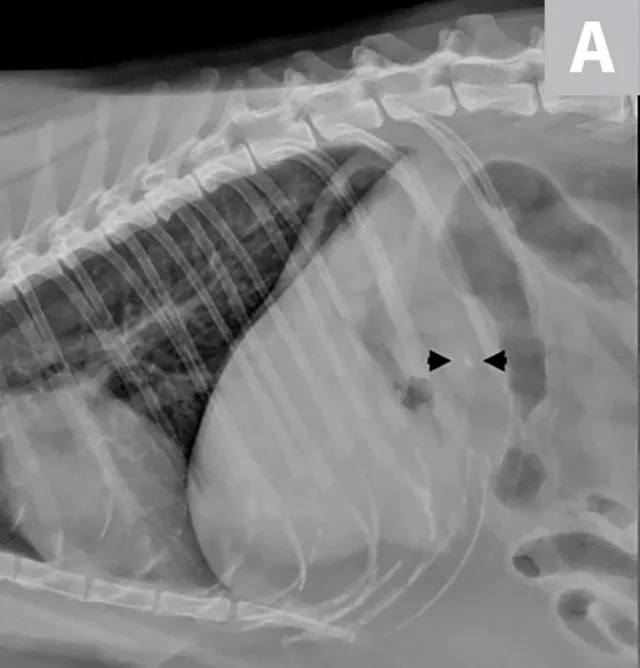

Lateral radiographs of a clinically normal cat (A) and a 14-year-old neutered male domestic shorthair cat (B) presented with icterus and elevated liver enzymes. A normal feline liver should have a sharp, pointed margin (A; arrows) and should not extend past the costal arch; the gastric axis should be parallel to the ribs (A; line). The liver in the icteric cat extends past the costal arch, and has rounded borders (B; arrows). The stomach is displaced caudally (B; line; gastric axis from the fundus to the antrum). An ovoid mineralization (B; arrowheads) is also superimposed with the cranioventral liver in the location of the gallbladder. This cat was diagnosed with cholangitis, lipidosis, and a cholelith.